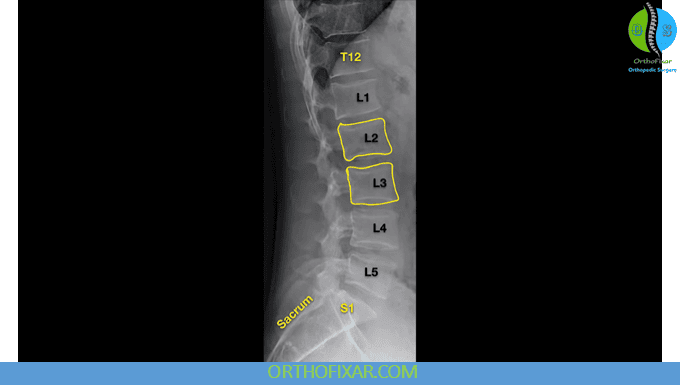

Lateral View

The lateral lumbar X-ray is essential for evaluating alignment, stability, and intervertebral spacing. The examiner should note:

- Spondylosis or spondylolisthesis (found in 2–4% of the population). The degree of vertebral slipping can be graded.

- Lumbar lordosis — normal curvature should be maintained.

- Intervertebral foramina — check for narrowing or distortion.

- Disc spacing — reduced space indicates disc degeneration.

- Alignment of vertebral bodies — loss of the smooth curve suggests spinal instability.

- Osteophyte formation or traction spurs — a traction spur develops about 1 mm from the disc margin and indicates instability, while an osteophyte forms directly at the vertebral margin.